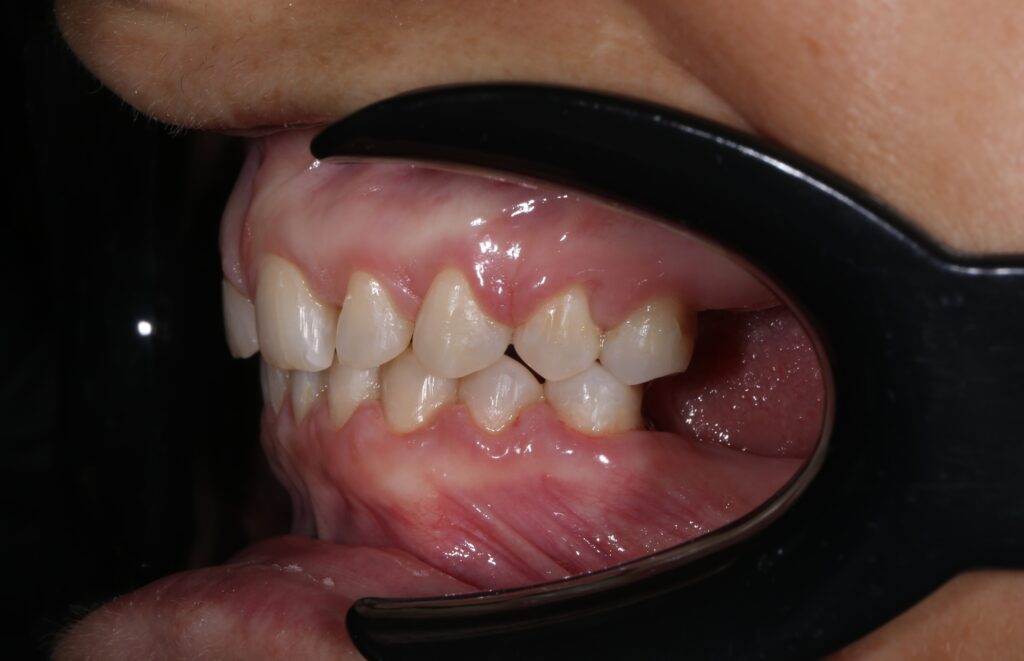

Ситуация до лечения

Пациентка 39 лет была направлена стоматологом-ортопедом для ортодонтической подготовки перед протезированием.

Из-за множественных давних удалений жевательных зубов, произошла деформация зубных рядов, зубы разъехались в область удаленных, что затрудняло протезирование в момент обращения к ортопеду.

Так же можно отметить сильное снижение высоты прикуса (верхние зубы на 100% перекрывали нижние, что вызывало хроническую травму десны), а также повышенную стираемость твердых тканей зубов,

что является следствием повышенной нагрузки, которую много лет испытывали передние зубы, в связи с отсутствием жевательных зубов.

пациент до брекетов